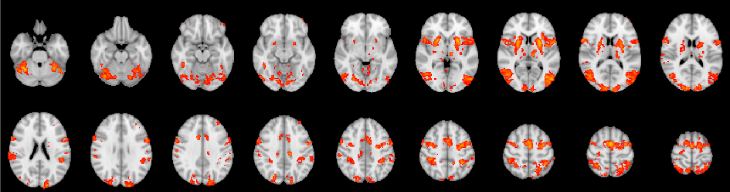

3.1 fMRI SMN mapping and BOLD time series extraction

The group-level maps of the SMN obtained for the motor imagery tasks (Graz and NeuRow) and the resting state (Rest) are shown in Fig. 3. An illustrative example of the fMRI time series obtained for the five conditions (Graz - TE, Graz - TBT, NeuRow - TE, NeuRow - TBT, and Rest) in an individual subject are shown in Fig. 4.